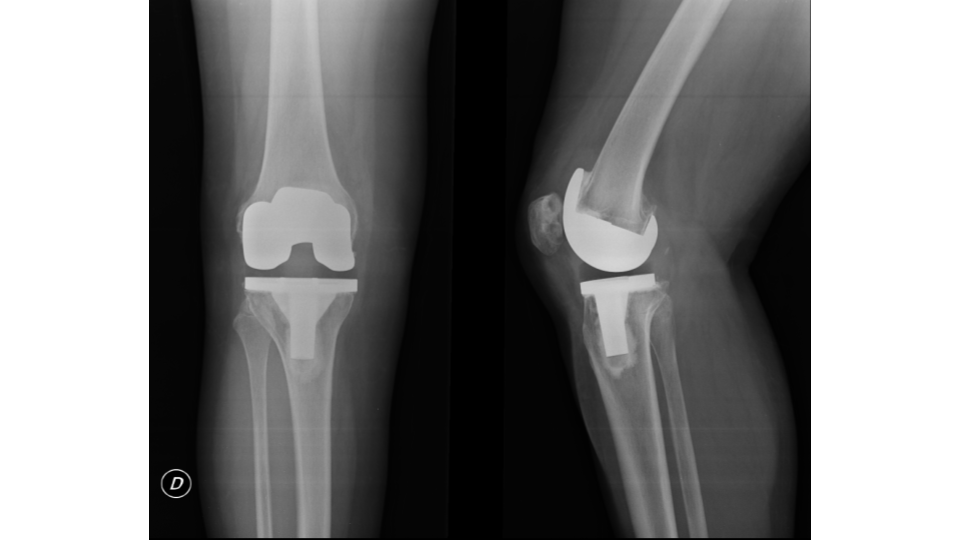

Se analizó un total de 36 prótesis en 32 pacientes. De este total, 25 (78 %) fueron de sexo femenino y 7 (22 %), de sexo masculino. Cuatro pacientes presentaron reemplazo bilateral (Figs. 1, 2 y 3).

Figura 3. Radiografía lateral postoperatoria tras artroplastia total de rodilla con prótesis cementada modelo Sigma (DePuy, Synthes/ Johnson & Johnson, Warsaw, IN, EE. UU.).